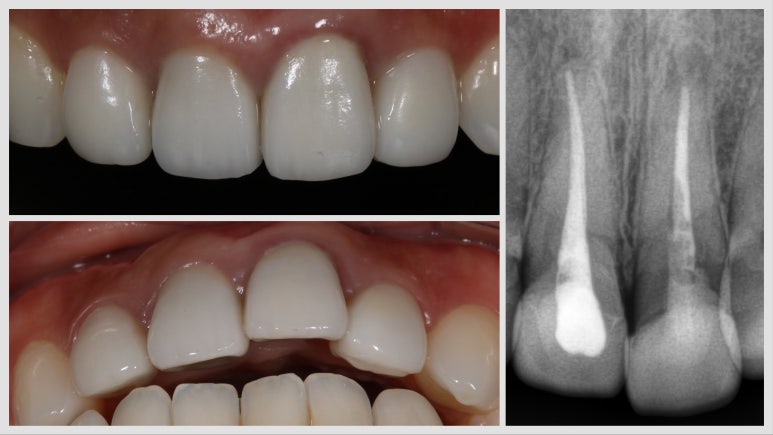

수술 4개월 후 - 잇몸 높이가 대칭이 맞아진 것을 볼 수 있습니다

위와 같이 잇몸 주위 조직이 건강하게 치유가 되고 옆 치아와 잇몸 높이 대칭성도 잘 맞게 아문 것을 확인할 수 있답니다.

보철물 완성 사진

마지막으로 보철물까지 올린 후에 완성 사진을 찍었답니다.

잇몸 높이가 옆 치아와 대칭성을 이루는 부분이 사실 가장 관건인데 이 부분이 잘 이루어진 것을 확인할 수 있답니다.

전후 비교 사진_ 잇몸 높이가 달랐던 술전 상황과는 달리 임플란트 수술 후에 잇몸 높이가 같아진 것을 확인할 수 있음

다행히 이렇게 케이스가 잘 마무리되었고요, 저희 병원 같은 경우 앞니 보철을 원내 제작하기 때문에 색조와 모양도 만족스럽게 마무리가 잘 되었답니다.